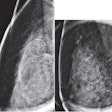

Using images from multiple health centers, the researchers collected data from 4,810 mammograms with 6,663 microcalcification lesions confirmed on biopsy. Of these, 3,301 were deemed to be malignant while 3,362 were benign.

The researchers found overall moderate to high classification values in training and test sets for differentiating between benign and malignant breast microcalcifications. These included high accuracy and area under the curve (AUC) values.

| Accuracy | 72% | 71% | 75% |

| AUC | 0.80 | 0.78 | 0.76 |

The team also reported that the sensitivity of malignant breast prediction reached 78%.